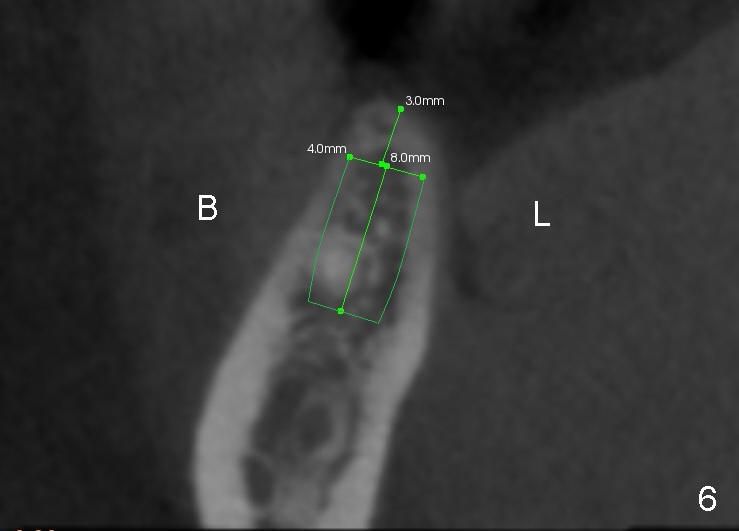

A 44-year-old lady has lost two of the 1st molars (upper left (Fig.1-3) and lower right (Fig.4-6)) for several years. Fig.1,4 are preop PAs, Fig.2,5 CT sagittal sections, and Fig.3,6 CT coronal sections. The adjacent teeth shift and tilt into the edentulous space.